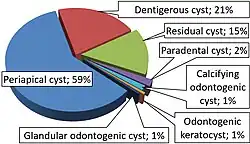

An odontogenic keratocyst is a rare and benign but locally aggressive developmental cyst. It most often affects the posterior mandible and most commonly presents in the third decade of life.[1] Odontogenic keratocysts make up around 19% of jaw cysts.[2] Despite its more common appearance in the bone region, it can affect soft tissue. [3]